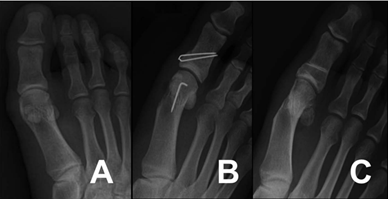

(八)病例示例

图10:A为术前X光,B和C分别为内固定和术后随访X光